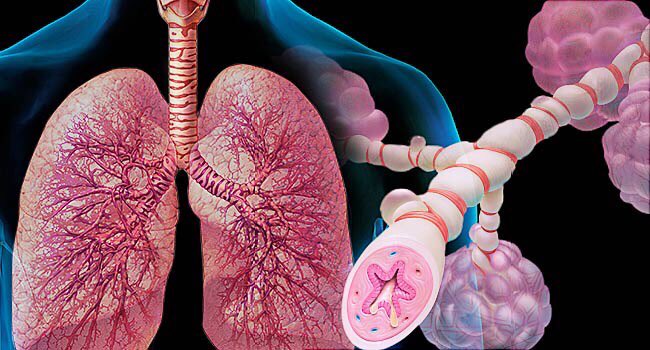

🔴اولا: ماهو مرض الربو ؟

Asthma is a chronic lung disease that inflames and narrows the airways. Asthma causes recurring periods of wheezing (a whistling sound when you breathe), chest tightness, shortness of breath, and coughing.

Asthma is a chronic lung disease that inflames and narrows the airways. Asthma causes recurring periods of wheezing (a whistling sound when you breathe), chest tightness, shortness of breath, and coughing.

The coughing often occurs at night or early in the morning

زبدة التعريف ان الازما (الربو ) هو مرض مزمن (يعني لفترة طويلة ) من صفات المرض التهاب وتضيق الشعب الهوائية يسبب صوت خفيف بصفير او ازيز وضيق بالتنفس

(عشان كذا نحتاج ادوية موسعة للشعب ومخففة للالتهاب 👌)

زبدة التعريف ان الازما (الربو ) هو مرض مزمن (يعني لفترة طويلة ) من صفات المرض التهاب وتضيق الشعب الهوائية يسبب صوت خفيف بصفير او ازيز وضيق بالتنفس

(عشان كذا نحتاج ادوية موسعة للشعب ومخففة للالتهاب 👌)